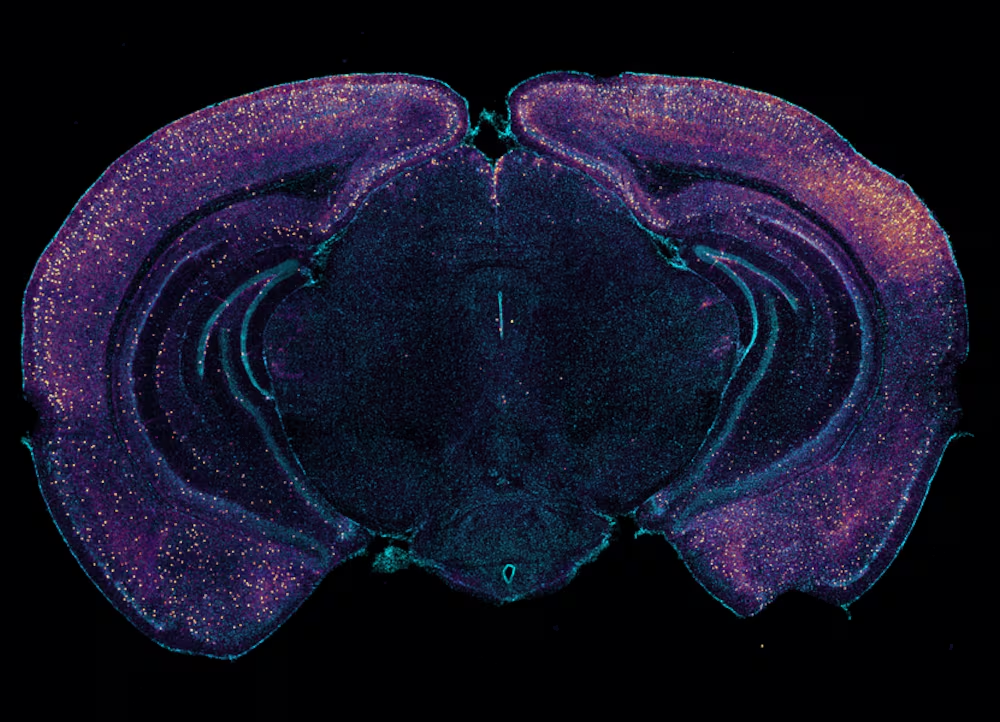

Un microbioma envejecido se caracteriza por tener altos niveles de algunas bacterias, entre ellas una llamada Parabacteroides goldsteinii, muestra el estudio. Cuando los científicos la trasplantaron a ratones jóvenes, vieron que su capacidad cognitiva también se resentía. Cuando los investigadores analizaron el cerebro de estos animales vieron que las neuronas de su hipocampo, uno de los epicentros de la memoria, mostraban menos actividad de lo normal. ¿Cómo pueden las bacterias intestinales afectar al cerebro? El trabajo demuestra que la conexión física y molecular es el nervio vago, cuya red de neuronas permite al cerebro sentir lo que sucede en el sistema digestivo, además de otros órganos claves, como el corazón o los pulmones.